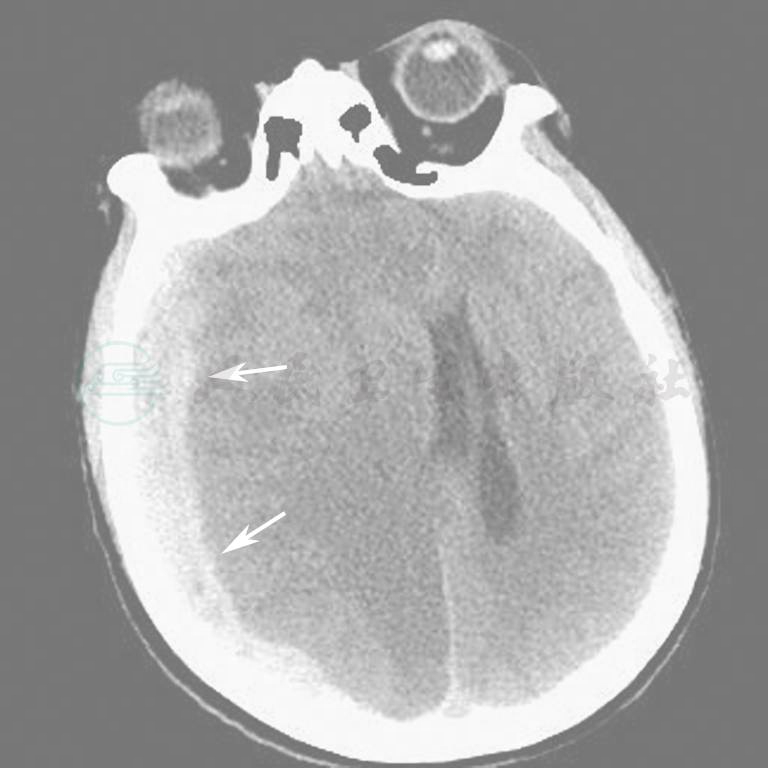

图11  双侧颅内出血(硬膜下)

图12  右侧颅内出血(硬膜下)

图13  右侧颅内出血(硬膜下)

图14  右侧慢性硬膜下出血